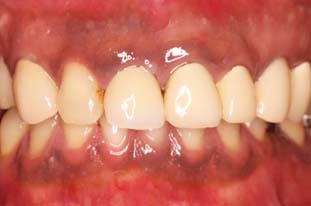

前歯のセラミック症例

| 主訴 | 前歯の色が変色していることが気になる。 (オールセラミック) |

| 年齢・性別 | 30代 男性 |

| 治療期間 | 約3週間 |

| リスク・副作用 | 噛む力が強い方の場合、セラミックが欠けてしまうことがあるので、就寝時にマウスピースを装着していただく必要があります。 |

| 治療内容 | オールセラミック |

| 治療本数 | 1本 |

| 治療費用 | 仮歯(テック)5,500円(税込) +かぶせ物代 (オールセラミック)110,000円(税込) |

| 治療方針 | ①歯の形態、かみ合わせ等を模型上で 診査、患者さまと相談した上で形態の決定 ②仮歯の装着 ③セラミックの試適(色・形の確認) ④セラミック装着 |

| ドクターのコメント | 治療後はセラミック治療による審美性は 獲得できましたが術前と比べ、 ホワイトニング後の後戻りがあり、 歯が黄ばんできているので、 ホワイトニング後のメンテナンスの 重要性をお伝え致しました。 |

治療過程

- 治療前

- 歯の形成後

- 仮歯装着後(2週間つけていたため変色している)

- 完成前の試適

- 治療終了後